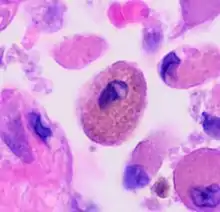

| Respiratory bronchiolitis | "Smoker’s macrophages" | Yellow to light brown and finely granular[4] | Airways (especially respiratory bronchioles) | Tobacco smoking |  |

Smoker's macrophage in center |